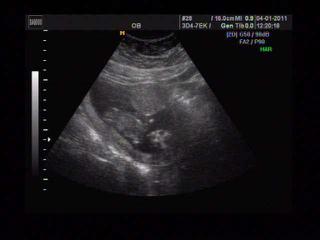

Kuratkol, krásný obrázek z ultrazvuku 😵 jak se cítíš?